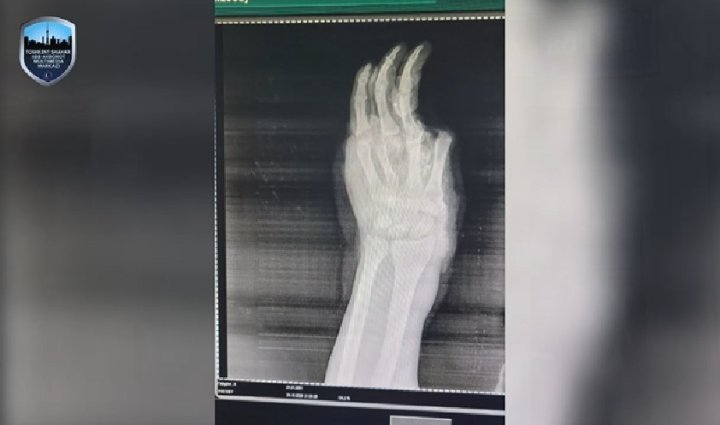

Сообщается, что на днях в Республиканский научный центр экстренной медицинской помощи поступил мальчик, проживающий в Янгихаётском районе. У мальчика было серьёзное повреждение кисти руки. Выяснилось, что у него в руке взорвалось пиротехническое изделие. В результате взрыва он получил ожоги различных частей тела. Также ему оторвало несколько пальцев на пострадавшей кисти, а кроме того, раздробило все кости. Из-за серьёзных повреждений тканей и раздробления всех костей, кисть руки пришлось ампутировать.